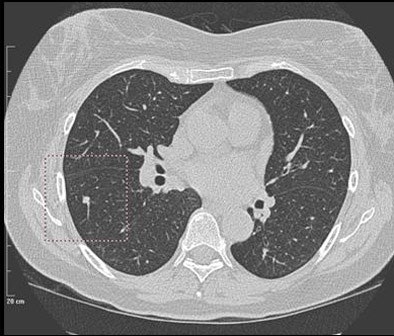

![]() |

| A 5-mm nodule in right middle lobe, representing a true-positive CAD finding. All images courtesy of Dr. Heidi Roberts. |